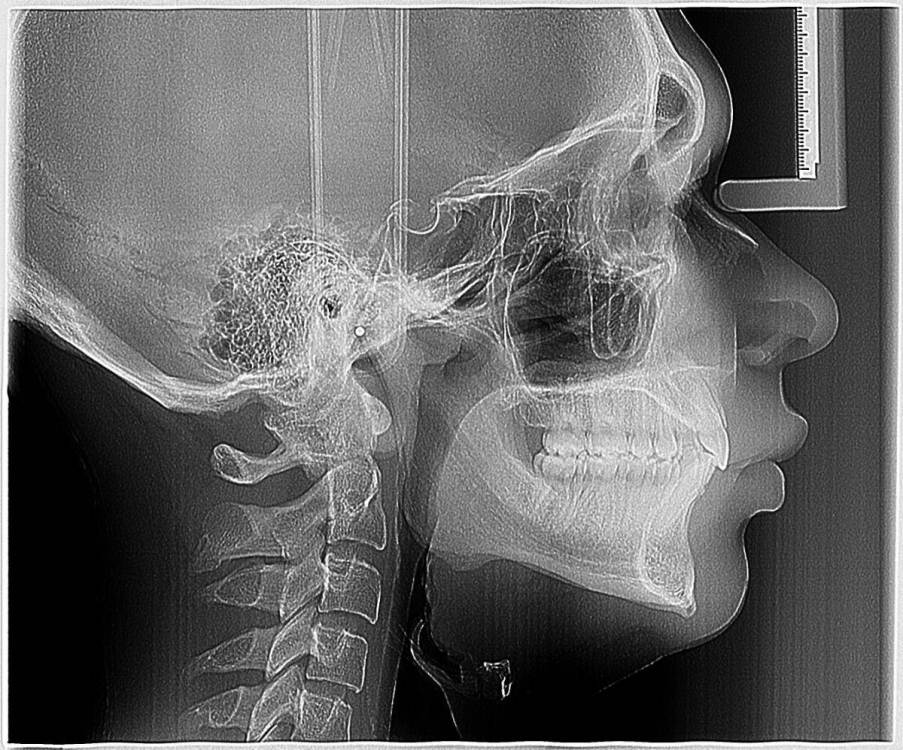

smikvarnik Опубликовано 12 июня, 2023 Поделиться Опубликовано 12 июня, 2023 (изменено) Здравствуйте, проблема следующая 25 лет, пол М У меня с детства аномалии(нет корней на 3х зубах), одна двойка справа молочная + тройки молочные. Двойка выпала и хожу с дыркой уже лет 10, также зона улыбки кривовата и есть промежуток между однерками тройки молочные маленькие но держатся, все хорошо. Самая главная проблема по которой мне многие отказывали в реставрации только зоны улыбки, это прикус. у меня глубокий прикус с детства. Ортодонты говорят что нужно носить брекеты 2-3 года, и только после этого имплантация либо коронки с мостами. Но пару ортопедов предложили мне сточить все верхние зубы(все жевательные зубы в отличном состоянии, передние так себе, уже немного сточены из за прикуса). Говорят что если поставить без исправления прикуса - я просто выбью коронки или импланты, нагрузка будет не такая какая должна быть Пробовал также ходить с капой чтобы поднять прикус - результатов нет. некоторые врачи отказывали даже в лечении брекетами, говоря что ситуация сложная. Также зубы для моего возраста маленькие, по сравнению с другими людьми Говорят что если сделать коронки на верхней челюсти, можно таким образом исправить прикус+сделать улыбку без ортодонтии. но также возможно потребуется сточить немного зубов на нижней(не уточнял какие) Коронки из диоксида циркония как вы считаете, это нормальный вариант, или так себе? у меня психологический комплекс из за зубов и еще 2-3 года ходить с брекетами и дырками честно говоря так себе идея. Какие есть минусы и опасности у такого варианта, и как с вашей точки зрения, как докторов, этот вариант оценивается? Насколько это целесообразно? Спасибо за помощь заранее, очень жду ответ, каждый день волнует эта тема Изменено 12 июня, 2023 пользователем smikvarnik Ссылка на комментарий

smikvarnik Опубликовано 13 июня, 2023 Автор Поделиться Опубликовано 13 июня, 2023 здравствуйте, не видел! исправляю еще также есть фото лица и самих зубов, как попросите так и сфоткаю. также есть КТ ВЧ и НЧ Ссылка на комментарий